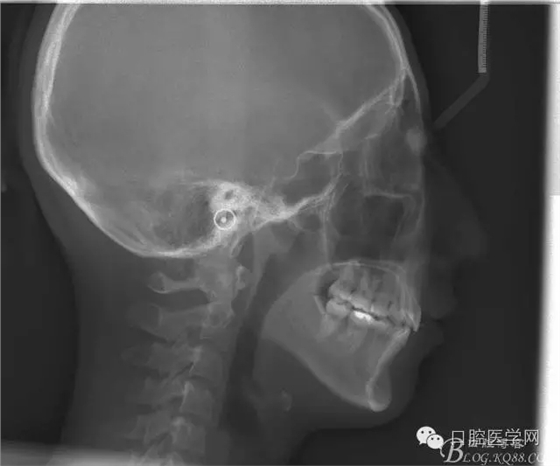

正畸前后頭顱側(cè)位SN平面和S點(diǎn)重疊圖: